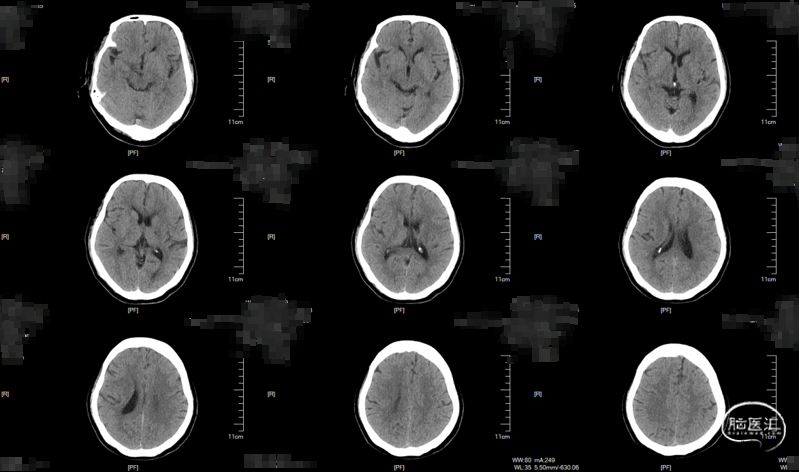

术中DynaCT。

术后4h CT。